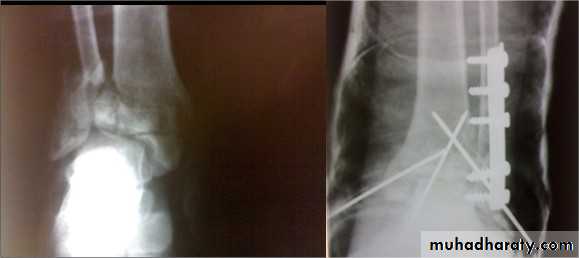

Calcaneal fractures

Usually after FFH.Associated injuries: spine, pelvis, hip or base of skull.

Extra-articular fractures: need closed treatment. Have good prognosis.

Intra-articular fractures:

involve superior articular surface. May be comminuted.

Treatment

Admit to hospital, elevate the leg and apply ice-packs until swelling subside.

Undisplaced fractures: closed treatment.

Displaced fractures: ORIF with screws.

Calcaneal tuberosity fracture